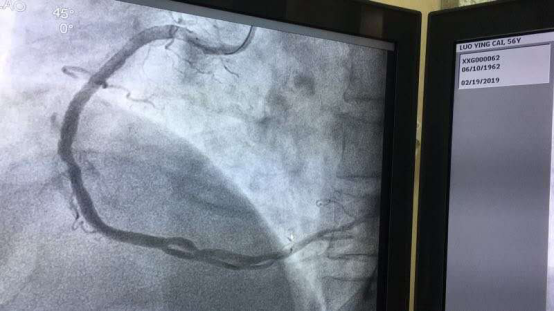

患者右冠状动脉近段全闭塞